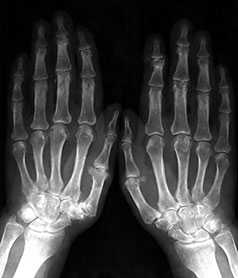

Рис. 3. Обзорная Rо-графия кистей.

Множественные артрозы дистальных и проксимальных межфаланговых суставов. Множественные узелки Гебердена и Бушара. Выраженный артроз 1-го левого запястнопястного сустава

Начальные проявления (соответствуют 1-2 стадиям артроза по Kellgren):

Небольшие заострения краев или остеофиты с нерезким субхондральным остеосклерозом; мелкие, субхондрально расположенные кисты при нормальной или слегка суженной суставной щели, мелкие кальцификаты в мягких тканях в области боковых краев суставных поверхностей костей.

Выраженные изменения (соответствуют 3-4 стадиям артроза по Kellgren):

Умеренно выраженные или крупные остеофиты, деформация краев суставных поверхностей, значительное сужение суставных щелей, остеосклероз (узелки Гебердена в дистальных межфаланговых суставах и узелки Бушара в проксимальных), кисты со склеротическим ободком, краевые дефекты суставных поверхностей, при этом костные выступы с одной стороны могут вклиниваться в другую. Обычно краевые дефекты окружены зоной остеосклероза (рис. 3).